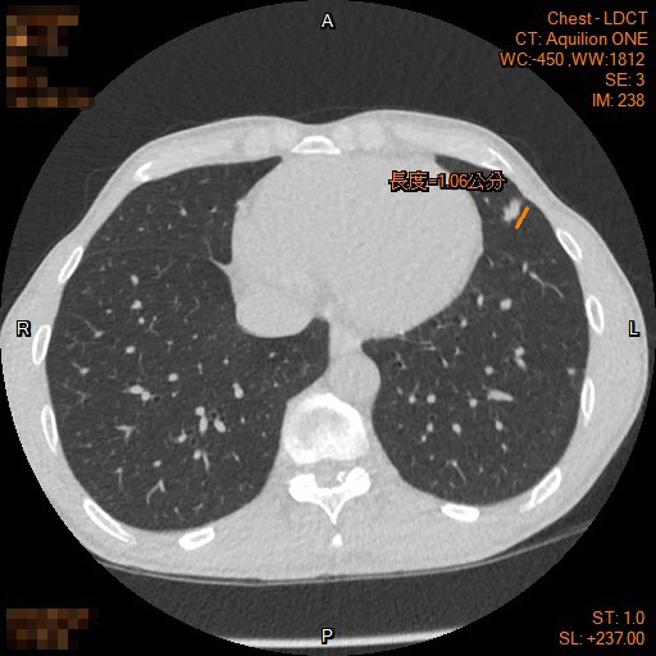

这次国民健国署补助的低剂量肺部电脑断层LDCT,是目前具国际实证,可以检测早期肺癌的有效工具。其优点是影像解析度与灵敏度较一般胸部X光高,但是辐射线的暴露量又较一般的电脑断层为低。高雄市立大同医院胸腔内科李岱晃医师表示,有些患者肿瘤虽然只有1公分,但在低剂量肺部电脑断层的检视之下,其恶性特徵非常明显,就必须尽早手术;也有些患者的肿瘤恶性特徵虽然不高,但是提早介入并定期追踪是否有变化,万一有变化时可早期介入处理。